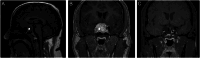

Summary: Functioning gonadotroph adenomas with clinical manifestations are extremely rare and the majority of these are FSH-secreting macroadenomas. Clinical symptoms are due to excess gonadotrophins and sex hormones, and these may be present for a long time before the diagnosis of pituitary adenoma is made. We present the case of a 37-year-old Caucasian male with clinical manifestations of an FSH-secreting pituitary macroadenoma. He had sexual dysfunction for a year followed by bilateral testicular pain and enlargement which was initially treated as suspected recurrent epididymitis, but his symptoms did not resolve. He presented a year later with headaches and bilateral superior temporal visual field defects. Brain imaging confirmed a pituitary macroadenoma with optic chiasm compression. Pituitary profile demonstrated an unusually high FSH with high normal LH and normal testosterone level. The patient successfully underwent transsphenoidal hypophysectomy and histology confirmed gonadotroph differentiation and immunoreactivity predominantly with FSH. Gonadotrophin levels and testosterone dropped significantly after surgery, and he was started on testosterone replacement. MR imaging, 2 years post surgery, showed no recurrence of pituitary adenoma. In conclusion, testicular enlargement and hypogonadal symptoms associated with low testosterone levels are recognised features in FSH-secreting pituitary adenomas. Our patient had hypogonadal symptoms but consistently high normal testosterone levels prior to surgery. The reason for low libido despite high testosterone is unclear. Our case highlights the need to suspect such rare underlying pituitary pathology when dealing with unusual combinations of hypogonadal symptoms, testicular enlargement with low or normal testosterone levels.

Learning points: Functioning pituitary adenomas that secrete excess follicle-stimulating hormone (FSH) are very rare and often present with symptoms related to pituitary mass effect. Testicular enlargement alongside sexual dysfunction are commonly reported symptoms amongst male patients. Pituitary profile results demonstrate a raised FSH level with either a low, normal, or even high testosterone level which may not always correlate to clinical symptoms. Pituitary pathology should be considered in males presenting with unusual combinations of testicular enlargement and hypogonadal symptoms even with normal testosterone levels.